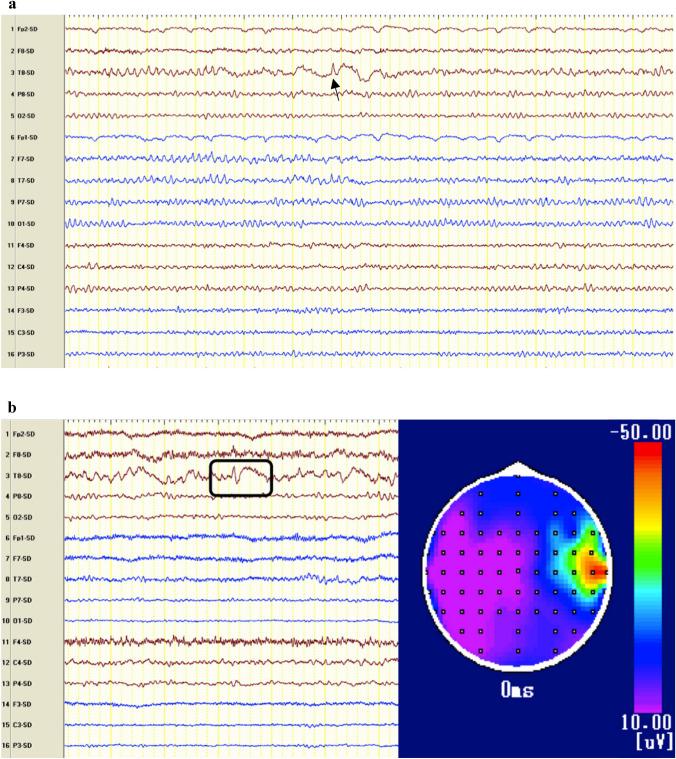

Stroke is the leading cause of seizures and epilepsy in older adults. Patients who have larger and more severe strokes involving the cortex, are younger, and have acute symptomatic seizures and intracerebral haemorrhage are at highest risk of developing post-stroke epilepsy. Prognostic models, including the SeLECT and CAVE scores, help gauge the risk of epileptogenesis. Early electroencephalogram and blood-based biomarkers can provide information additional to the clinical risk factors of post-stroke epilepsy. The management of acute versus remote symptomatic seizures after stroke is markedly different. The choice of an ideal antiseizure medication should not only rely on efficacy but also consider adverse effects, altered pharmacodynamics in older adults, and the influence on the underlying vascular co-morbidity. Drug-drug interactions, particularly those between antiseizure medications and anticoagulants or antiplatelets, also influence treatment decisions. In this review, we describe the epidemiology, risk factors, biomarkers, and management of seizures after an ischaemic or haemorrhagic stroke. We discuss the special considerations required for the treatment of post-stroke epilepsy due to the age, co-morbidities, co-medication, and vulnerability of stroke survivors.